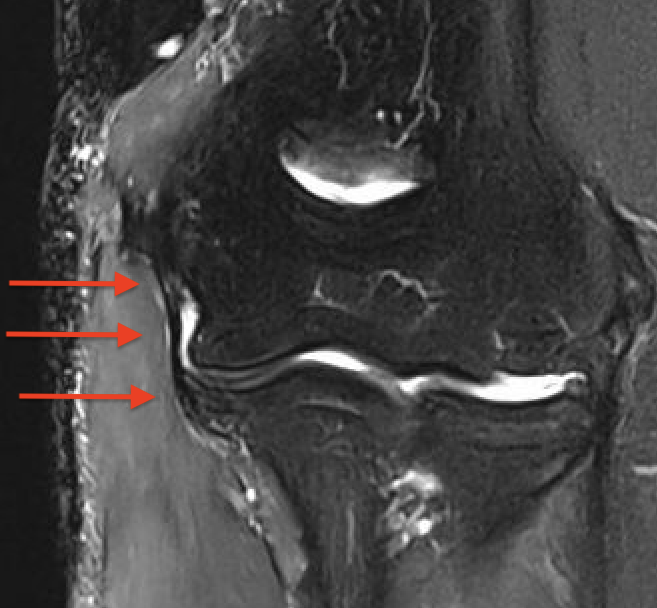

MRI

Intact

UCLUCL

Grading of tears

Proximal / midsubstance / distal injury

Partial tears - low grade versus high grade

Complete tears